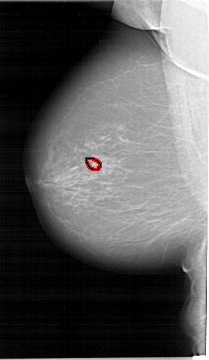

FILE: A_1649_1.LEFT_MLO.OVERLAY

TOTAL_ABNORMALITIES 1

ABNORMALITY 1

LESION_TYPE CALCIFICATION TYPE PLEOMORPHIC DISTRIBUTION CLUSTERED

ASSESSMENT 4

SUBTLETY 4

PATHOLOGY BENIGN

TOTAL_OUTLINES 1